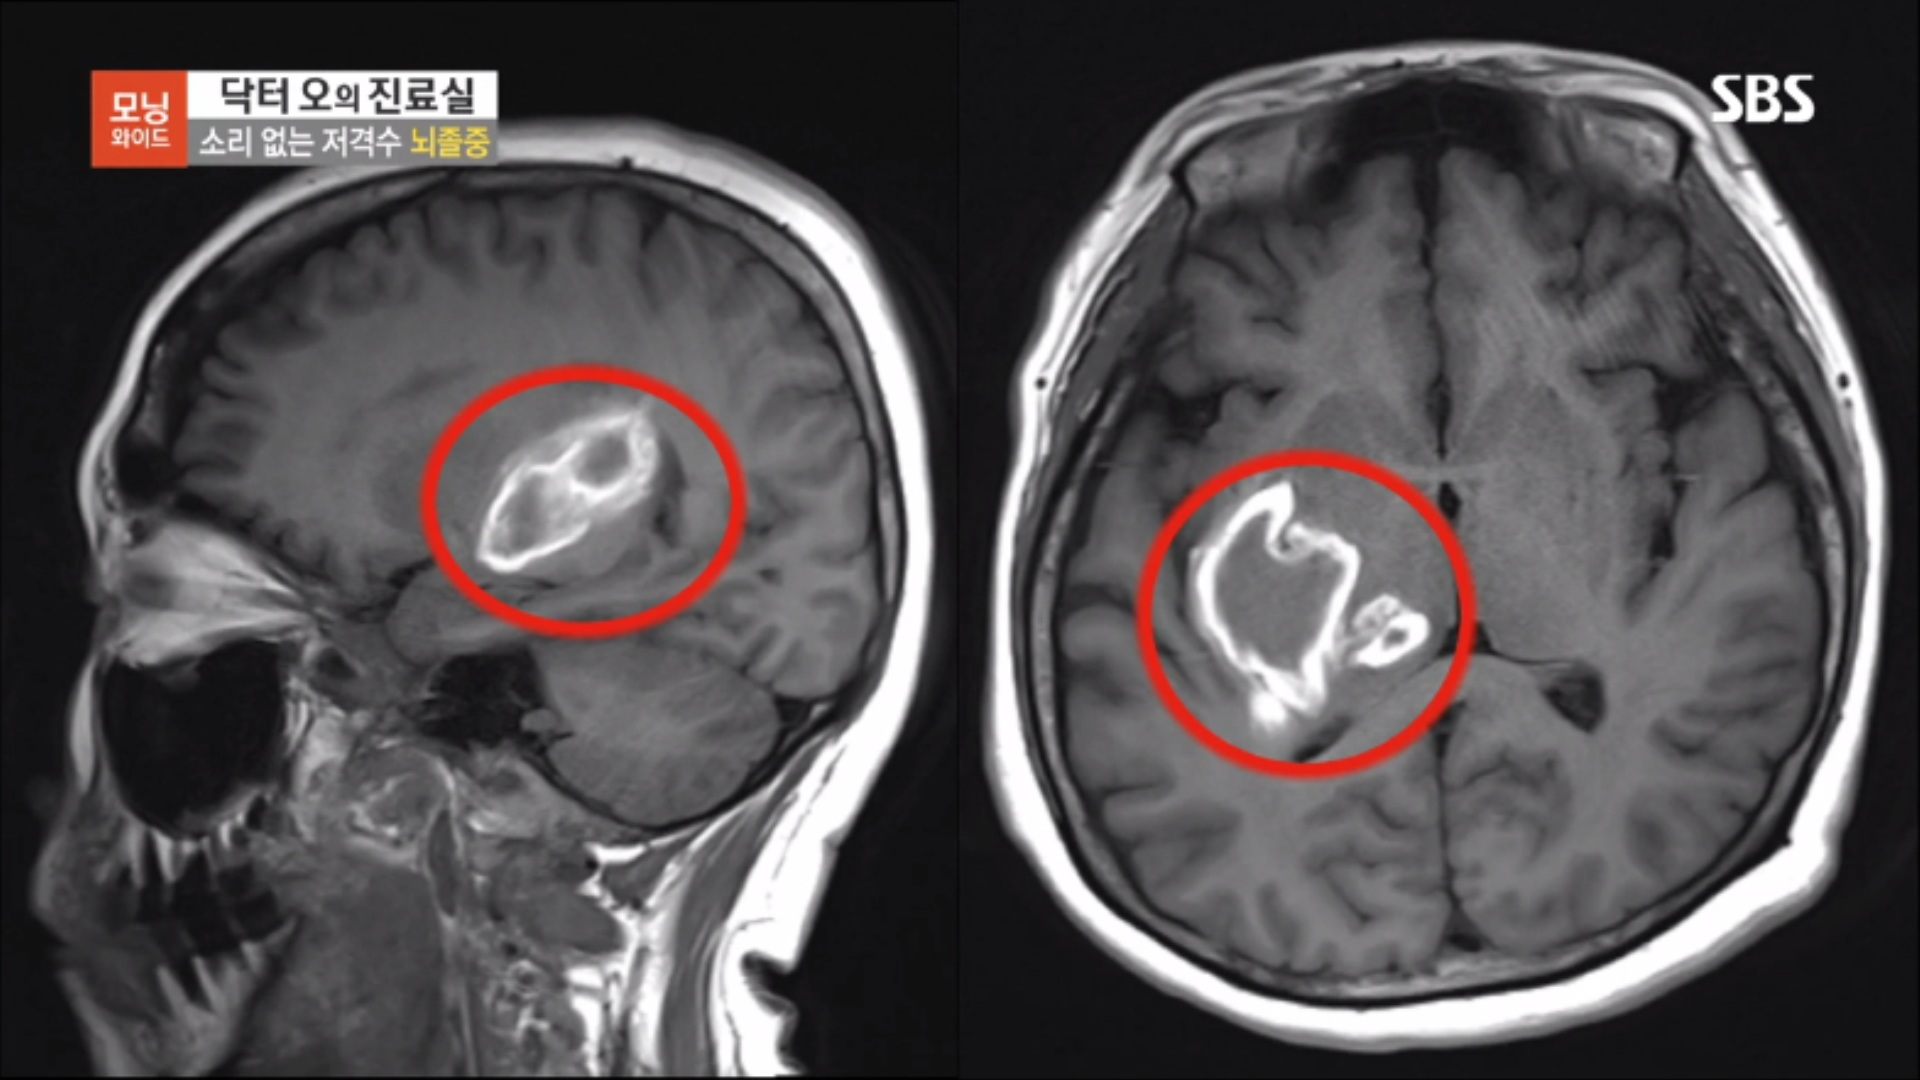

환자분은 우측 뇌출혈에 의해서 좌측 편마비가 발생한 상태였습니다.

우리가 흔히 알고 있는 것처럼 '우뇌'는 좌측 신체를 관장하고 '좌뇌'는 우측 신체를 관장하게 되는데요. 환자분처럼 우측 뇌 일부가 손상된 경우에는 좌측 신체를 마음대로 쓰지 못하는 편마비(반신불수) 장앵가 발생할 수 있습니다.